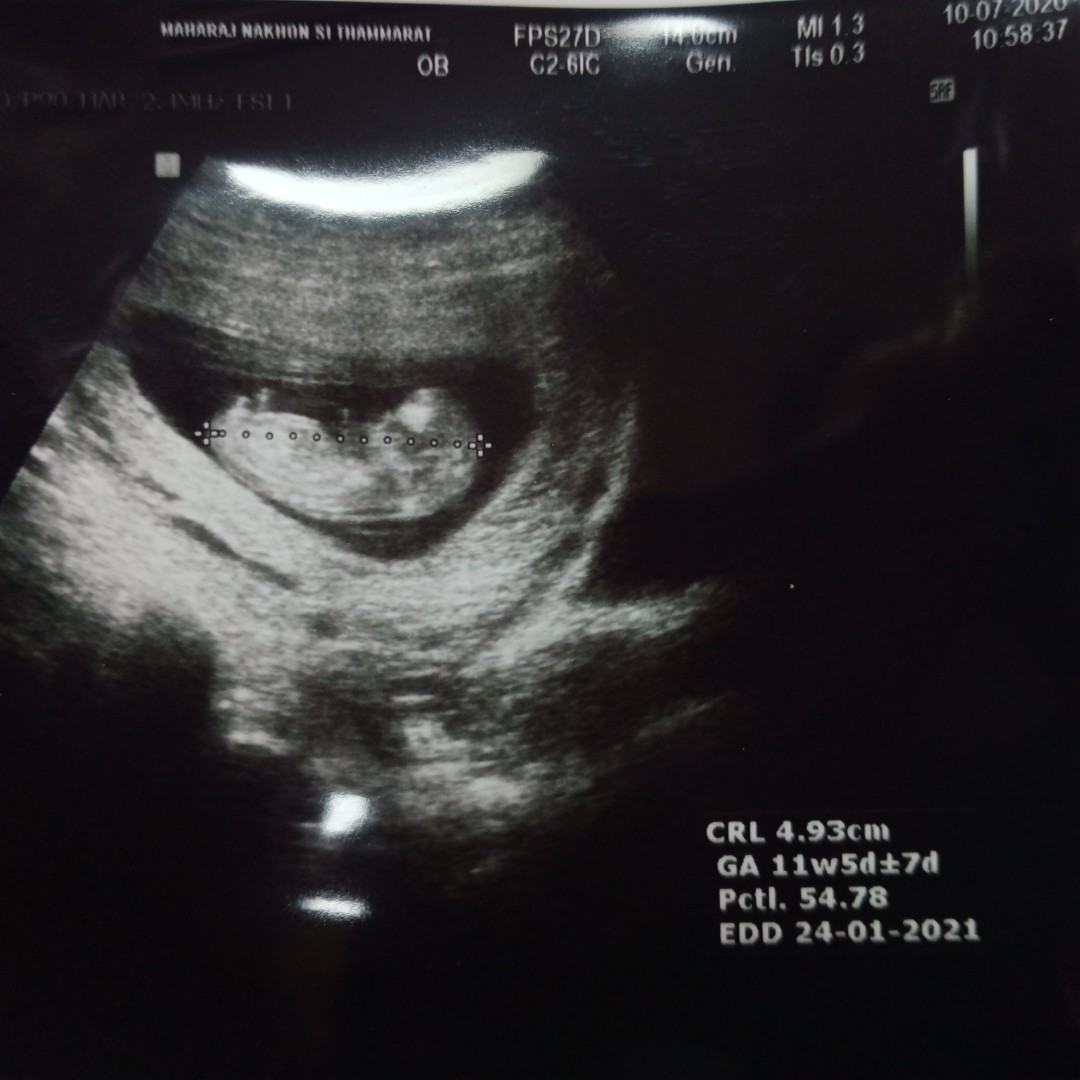

ขอเสียงคุณแม่เดือน มกราคม จ้า แม่บ้านนี้ได้ ผู้ชาย🤰🤰🤰👪